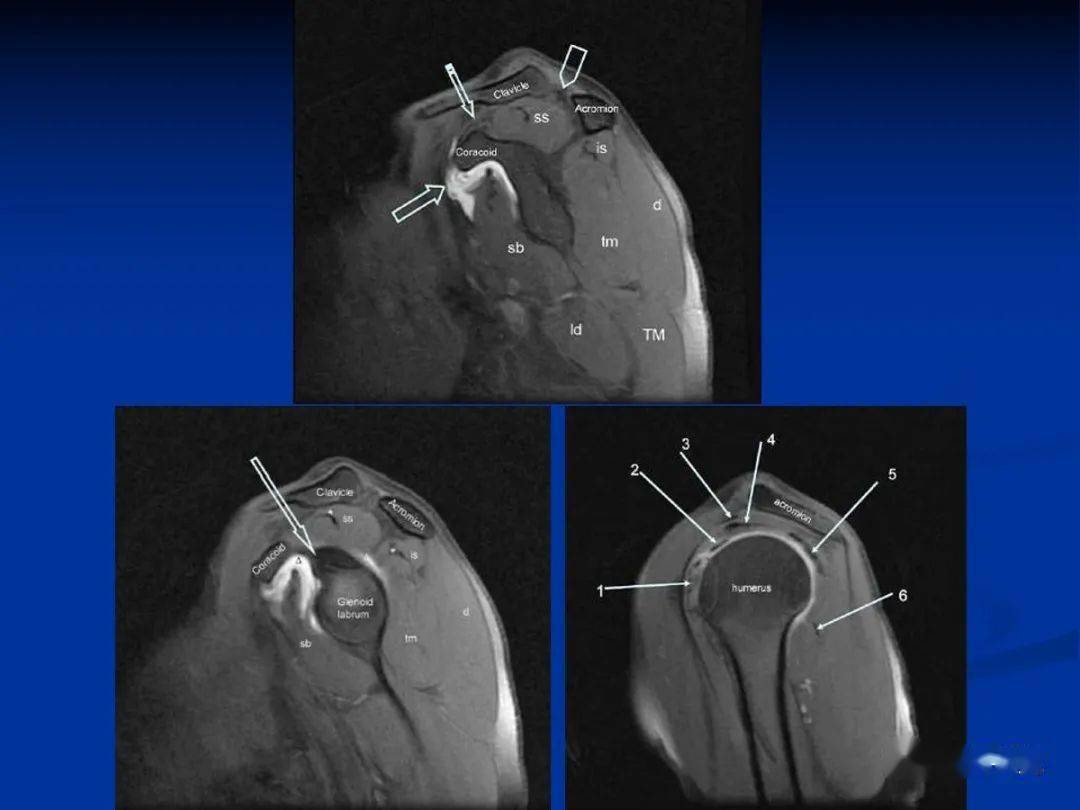

影像解剖肩关节磁共振断层